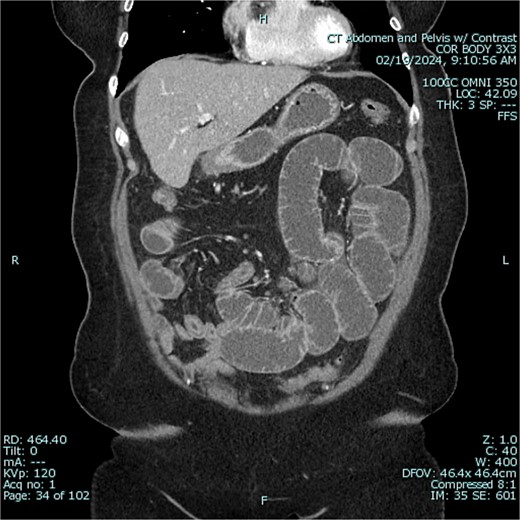

A 67-year-old female patient with a past medical history significant only for C-section, presented with 1 week of intermittent abdominal pain, distension, and nausea with vomiting. Vital signs were in the normal range. Physical exam was notable for a soft and nondistended abdomen with right lower quadrant tenderness. Laboratory studies were unremarkable. Radiological imaging (Figs 1 and 2) demonstrated a developing SBO.

Preoperative CT of abdomen in coronal view, demonstrating small bowel obstruction.